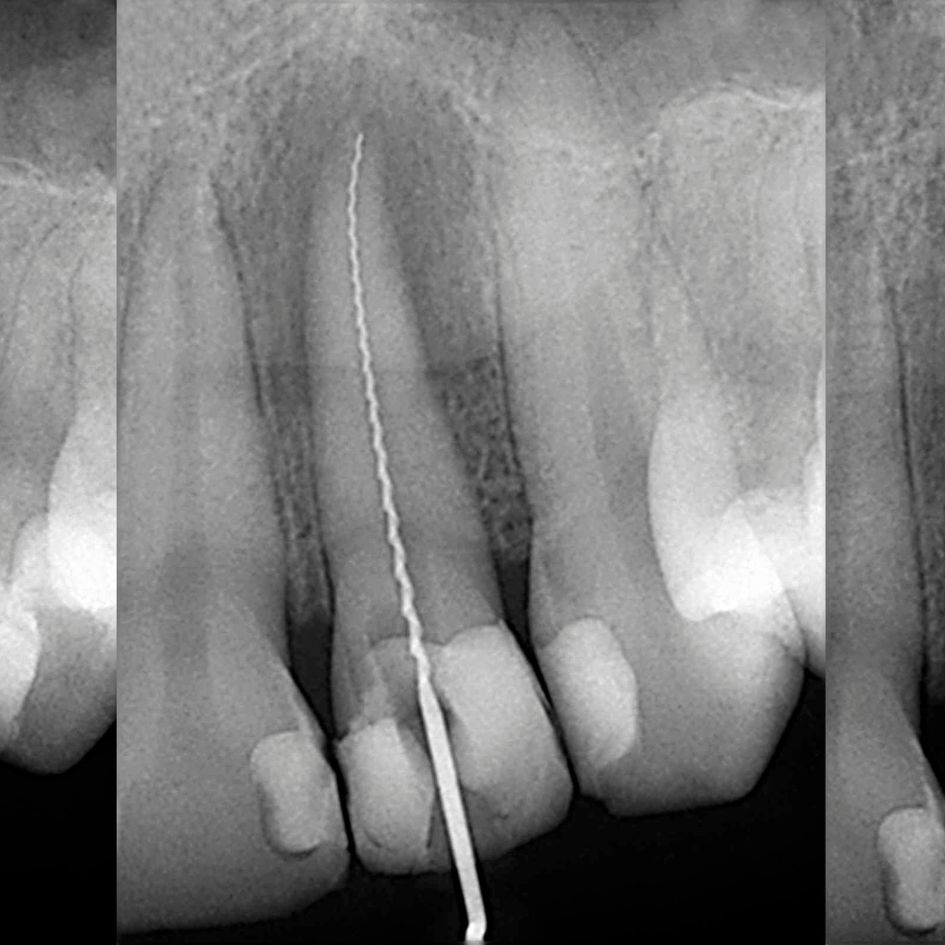

El diagnóstico de una endodoncia es un paso crucial para identificar y tratar problemas en la pulpa dental antes de que se conviertan en complicaciones mayores. En la Clínica Dental del Dr. Sánchez Solís, realizamos evaluaciones detalladas utilizando tecnología avanzada para garantizar un diagnóstico preciso y ofrecerte el mejor tratamiento. Descubre cómo se realiza el diagnóstico y qué señales pueden indicar que necesitas una endodoncia.